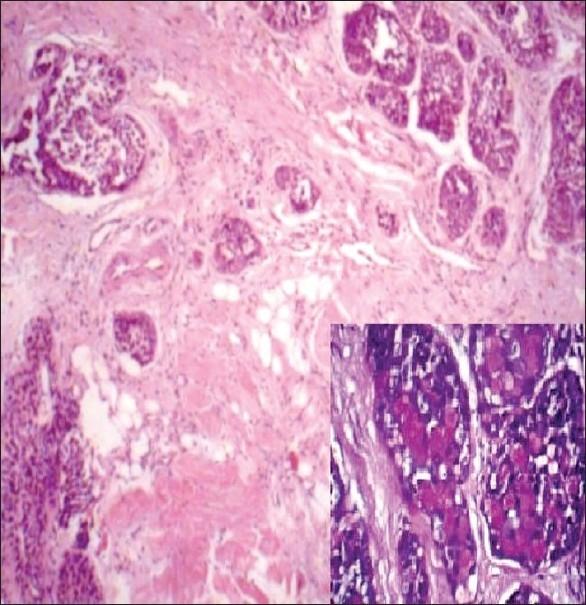

Basal-cell adenoma and basal-cell adenocarcinoma of the salivary gland are rare tumors. Fine-needle aspiration cytology of these tumors, particularly those of basal-cell adenocarcinoma, has rarely been described in the literature. In this report, we describe the clinical, cytomorphologic and histopathologic features of basal cell adenocarcinoma in a 48-year-old male patient. Fine-needle aspiration specimen showed abundant cohesive groups of basaloid cells revealing focal anisonucleosis and nuclear atypia. The tumor cells also showed rosette-like arrangement around central eosinophilic globule. Pertinent literature is reviewed and differential diagnosis are discussed.

涎腺基底细胞腺瘤和基底细胞腺癌是罕见肿瘤。这些肿瘤的细针穿刺细胞学检查,尤其是基底细胞腺癌的细针穿刺细胞学检查,在文献中很少被描述。在本报告中,我们描述了一名48岁男性患者基底细胞腺癌的临床、细胞形态学和组织病理学特征。细针穿刺标本显示大量紧密聚集的基底样细胞,可见局灶性核大小不一和核异型性。肿瘤细胞还围绕中央嗜酸性小球呈玫瑰花结样排列。回顾了相关文献并讨论了鉴别诊断。